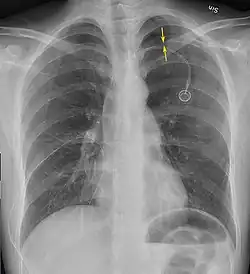

Una radiografía realizada en proyección postero-anterior (de atrás hacia delante) y durante la inspiración máxima constituye la forma de diagnóstico más frecuente.[38] Las imágenes realizadas en espiración, al contrario, no poseen valor diagnóstico significativo,[20] aunque pueden resultar útiles cuando existe una alta sospecha de neumotórax, pero la radiografía en inspiración aparece normal.[39] Si este es el caso, también pueden realizarse radiografías de proyección lateral, aunque esta práctica no se realiza con frecuencia.[20][31]

-

radiografía anteroposterior que muestra un neumotórax de reducido tamaño en el pulmón izquierdo, causado por una punción -

Radiografía lateral en inspiración, que muestra el neumotórax en la parte posterior -

Radiografía anteroposterior en espiración en la que también puede observarse el neumotórax

A veces puede darse una desviación del mediastino hacia el lado contrario en el que se halla el neumotórax debido a las diferencias de presión que crea esta patología. La presencia de esta desviación no implica la existencia de un neumotórax a tensión, que habitualmente se diagnostica a través de signos de gravedad como hipoxia severa y choque obstructivo.[30]

El tamaño del neumotórax (es decir, la cantidad que este ocupa en la cavidad pleural) puede determinarse midiendo la distancia entre la caja torácica y el borde del pulmón. Esto es de relevancia para el tratamiento, ya que los neumotórax de menor tamaño a menudo poseen un enfoque terapéutico distinto. Una distancia de dos centímetros significa que el neumotórax ocupa un 50 % del hemitórax.[20] Las guías de práctica clínica afirman que esta medida debe darse a partir del hilio pulmonar, con un umbral de referencia de dos centímetros para indicar la presencia de un neumotórax de menor o mayor tamaño. La medida también puede realizarse a partir del ápice pulmonar, y en este caso el umbral es de tres centímetros,[40] aunque esta forma de medición puede hacer pensar que el tamaño del neumotórax es mayor si este se encuentra concentrado en la parte superior de la caja torácica.[20][31] Aun teniendo en cuenta esto, estos métodos de medida no poseen una correlación perfecta con el tamaño del neumotórax y, aunque el TAC ofrece imágenes más precisas en este sentido, se desaconseja su uso en estas situaciones clínicas.[20]

No todos los neumotórax son uniformes; algunos ocupan solamente un pequeño espacio en un espacio particular de la cavidad pleural.[20] A veces, pueden hallarse pequeñas cantidades de líquido en la radiografía (hidroneumotórax), que puede estar constituido por sangre (hemoneumotórax).[30] En algunos casos la única manifestación de estos que se da en la radiografía es el signo del surco profundo, por el cual se da un aumento del espacio entre la caja torácica y el diafragma por la presencia de líquido.[35]